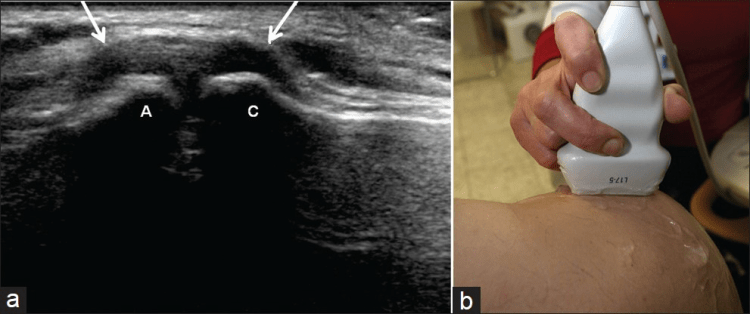

La ecografía del hombro comienza examinando el surco bicipital (BG) y la cabeza larga del tendón del bíceps braquial. El paciente está sentado frente al operador en una posición neutra, su mano colocada con la palma hacia arriba sobre el muslo. Se realiza una imagen de eje corto colocando el transductor sobre la metáfisis humeral proximal perpendicular al húmero. La imagen del eje largo del tendón se obtiene girando el transductor a una posición paralela a la diáfisis humeral [Figura 1]. Luego, se examina el tendón del subescapular. El brazo del paciente se fija sobre el flanco y el antebrazo se abduce en rotación externa. Se realizan vistas de eje largo y corto del tendón [Figura 2]. Los tendones infraespinoso y redondo menor se examinan desde una vista posterior del hombro. El paciente se gira 90°, su mano se coloca sobre el hombro opuesto y el transductor se orienta en el plano axial sobre la cabeza del húmero [Figura 3]. La articulación glenohumeral y la escotadura espinoglenoidea también se examinan en una vista posterior del hombro. El transductor ahora se mueve medial y caudalmente en el plano transversal hasta que se vea el margen posterior de la articulación glenohumeral y luego, más medialmente para mostrar la escotadura espinoglenoidea [Figura 4]. El tendón supraespinoso se escanea en una vista anterior del hombro. El paciente está sentado frente al operador. El brazo del paciente se coloca en una posición posterior, la mano dorsal en el ala ilíaca opuesta o la mano palmar en el ala ilíaca ipsilateral. Se obtienen vistas de eje largo y corto del tendón supraespinoso. Luego se realiza la exploración del manguito de los rotadores durante las maniobras dinámicas. El transductor se coloca sobre el acromion. El brazo del paciente se abduce con el codo flexionado a 90° o/y el brazo se extiende anteriormente [Figura 5]. Finalmente, se escanea la articulación acromioclavicular. La mano del paciente se coloca con la palma hacia arriba sobre el muslo. El transductor se coloca sobre la parte superior del hombro en un plano coronal [Figura 6].